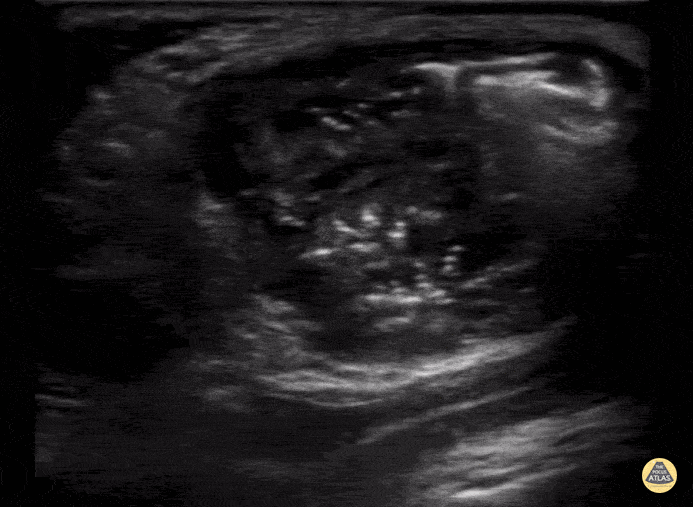

Peds-Genitourinary - Inguinal Hernia into Scrotum

2 week old with scrotal swelling found to have indirect inguinal hernia. Bowel contents can be seen present in this clip in the scrotum with some surrounding fluid. Contributor: Kathryn Pade, MD